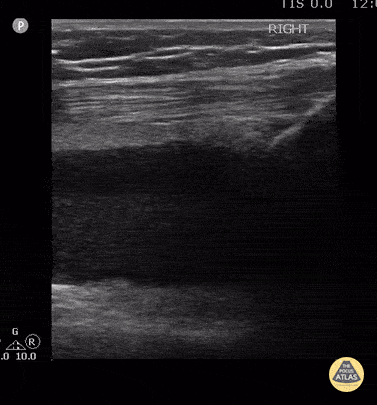

This is the long axis view of the case series. 15 year old female with patella fracture after a fall. Note the large suprapatellar effusion with discrete layering of the echogenic marrow/adipose above the acute hypoechoic blood. The lipohemarthrosis is visible in long and short axis. Contributor: Antonio Riera, MD Yale University School of Medicine